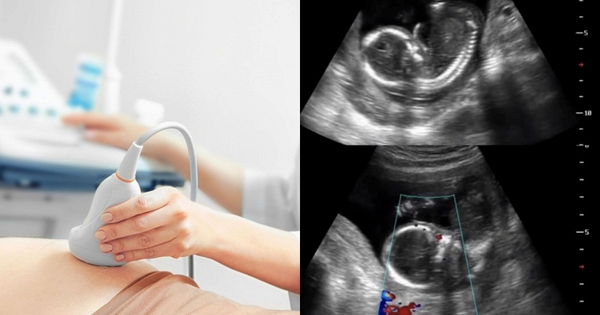

Trong thai kỳ, đặc biệt là những trường hợp có chỉ định dưỡng thai, việc di chuyển đường dài và lao động nặng có thể làm gia tăng nguy cơ biến chứng nghiêm trọng.

Cụ thể, ngồi xe lâu liên tục dễ gây mệt mỏi, tụ máu vùng chậu, rối loạn tuần hoàn máu, từ đó ảnh hưởng đến việc cung cấp oxy và dưỡng chất cho thai nhi. Với những thai phụ có tiền sử dọa sảy, dọa sinh non hoặc thai yếu, việc di chuyển xa càng tiềm ẩn rủi ro cao.

Bên cạnh đó, làm việc quá sức, đứng lâu, cúi gập người, bê vác nặng hoặc căng thẳng kéo dài có thể làm tăng co bóp tử cung, dẫn đến dọa sảy thai, sinh non hoặc thai lưu. Stress tâm lý cũng là yếu tố nguy hiểm, bởi nó có thể ảnh hưởng đến nội tiết và gián tiếp tác động xấu đến thai nhi.

Mỗi thai kỳ là một hành trình cần được theo dõi và bảo vệ nghiêm ngặt. Khi bác sĩ đã chỉ định nghỉ ngơi, gia đình tuyệt đối không nên ép thai phụ di chuyển hay lao động vì bất kỳ lý do nào, kể cả những lý do mang tính truyền thống hay trách nhiệm gia đình.